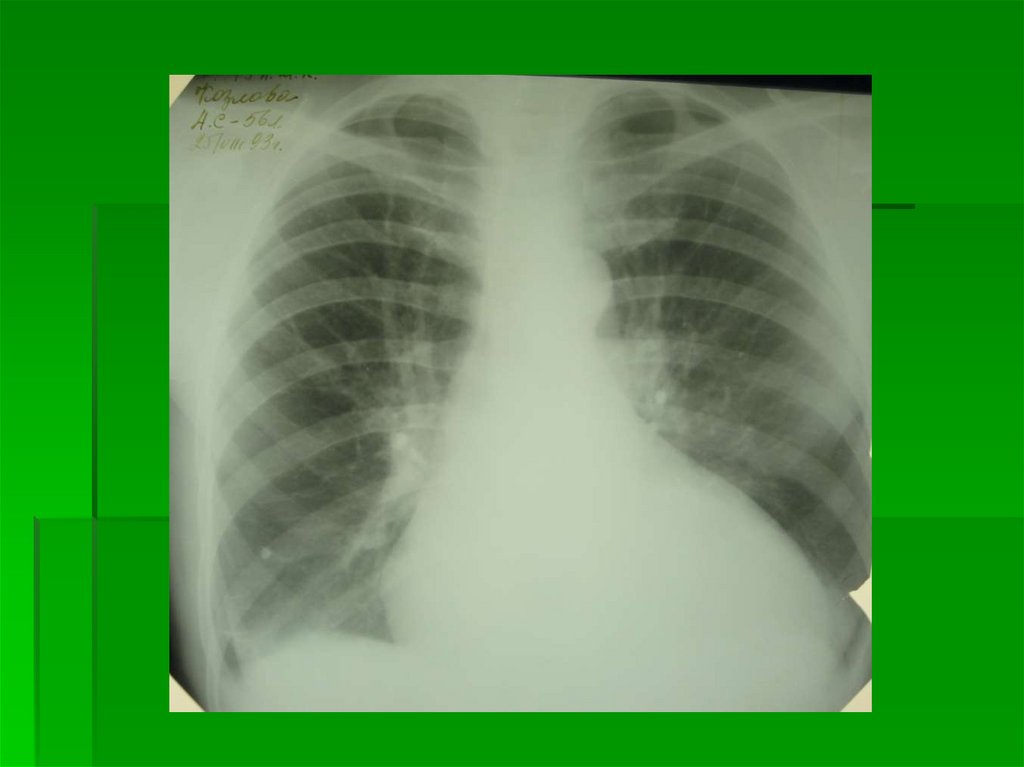

2 степень

Диффузный легочновенозный застой

P = 15-25 мм рт. ст

Симптомы перераспределения +

Корни неструктурны за счет проекционного наслоения

увеличенного количества сосудов в ортогональной

проекции

По всем легочным полям определяются расширенные

венозные стволы, их интенсивность и плотность

меньше интенсивности и плотности артериальных

стволов

Наружные контуры сосудов могут быть как четкие, так и

нечеткие (в зависимости от P в легочных венах)

2 степень Диффузный

легочно-венозный застой